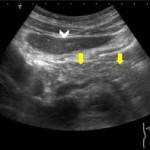

Actualmente, "existen herramientas invasivas y no invasivas para evaluar los depósitos de grasa intrapancreáticos", indica Verdejo, al tiempo que añade que algunas de estas herramientas cuentan con una alta precisión, como son la resonancia magnética, la tomografía computarizada y la ecoendoscopia. Sin embargo, "la evaluación de los depósitos de grasa intrapancreática requiere de un método de examen estandarizado con valores de corte significativos y validados prospectivamente que, hoy en día, no tenemos", confirma.

Por último, la SEPD ha explicado que la esteatosis pancreática es una infiltración de tejido graso en las células del páncreas que puede ser local, afectando solo a una parte del páncreas, o difusa afectando a la totalidad del órgano.

En este sentido, apunta, la penetración difusa tiende a tener un mayor impacto sistémico y puede asociarse a complicaciones metabólicas y neoplásicas más graves, mientras que la penetración localizada puede estar vinculada a condiciones más específicas y focalizadas. Con esto, el grado de infiltración de grasa afecta considerablemente a las implicaciones clínicas que conllevan. Cuando se produce el reemplazo graso, se cree que ya es irreversible, debido a la muerte de las células acinares pancreáticas.